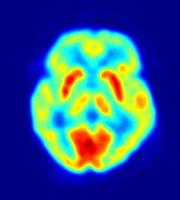

Pozytonowa Tomografia Emisyjna jest techniką obrazowania, w której (zamiast jak w tomografii komputerowej ? zewnętrznego źródła promieniowania rentgenowskiego lub radioaktywnego) rejestruje się promieniowanie powstające podczas anihilacji pozytonów (anty-elektronów). Źródłem pozytonów jest podana pacjentowi substancja promieniotwórcza, ulegająca rozpadowi beta plus. Substancja ta zawiera krótko żyjące izotopy promieniotwórcze, dzięki czemu większość promieniowania powstaje w trakcie badania, co ogranicza powstawanie uszkodzeń tkanek wywołanych promieniowaniem. Wiąże się także z koniecznością uruchomienia cyklotronu w pobliżu (krótki czas życia izotopów to także krótki maksymalny czas ich transportu) co znacząco podnosi koszty.

ZASADY DZIAŁANIA?

Powstające w rozpadzie promieniotwórczym pozytony, po przebyciu drogi kilku milimetrów, zderzają się z elektronami zawartymi w tkankach ciała, ulegając anihilacji. W wyniku anihilacji pary elektron ? pozyton powstają dwa kwanty promieniowania elektromagnetycznego (fotony) poruszające się w przeciwnych kierunkach (pod kątem 180°) i posiadają energię o wartości 511 keV każdy. Fotony te rejestrowane są jednocześnie przez dwa z wielu detektorów ustawionych pod różnymi kątami w stosunku do ciała pacjenta (najczęściej w postaci pierścienia), w wyniku czego można określić dokładne miejsce powstania pozytonów. Informacje te rejestrowane w postaci cyfrowej na dysku komputera, pozwalają na konstrukcję obrazów będących przekrojami ciała pacjenta, analogicznych do obrazów uzyskiwanych w tomografii NMR.

W badaniu PET wykorzystuje się fakt, że określonym zmianom chorobowym towarzyszy podwyższony metabolizm niektórych związków chemicznych, np. cukrów. Ponieważ energia w organizmie uzyskiwana jest głównie poprzez spalanie cukrów, to w badaniach wykorzystuje się deoxyglukozę znakowaną izotopem F-18.

ZASTOSOWANIE?

PET stosuje się w medycynie nuklearnej głównie przy badaniach mózgu, serca, stanów zapalnych niejasnego pochodzenia oraz nowotworów.Umożliwia wczesną diagnozę choroby Huntingtona. Zastosowanie PET wpłynęło na znaczne poszerzenie wiedzy o etiologii i przebiegu w przypadku choroby Alzheimera, Parkinsona czy różnych postaci schizofrenii.

Dzięki diagnostyce PET istnieje bardzo duże prawdopodobieństwo rozpoznania nowotworów (w około 90% badanych przypadków). Takiego wyniku nie daje się osiągnąć przy pomocy żadnej innej techniki obrazowania. PET daje także możliwość kontroli efektów terapeutycznych w trakcie leczenia chorób nowotworowych, np. za pomocą chemioterapii.

KORZYŚCI?

Emisja tomograficzna pozytonowa pozwala ocenić nie tylko kształt organów i tkanek, ale także ich funkcjonowanie. Zmiany w tkankach można zatem wykryć wcześniej, niż pozwala na to tomografia komputerowa bądź rezonans magnetyczny.